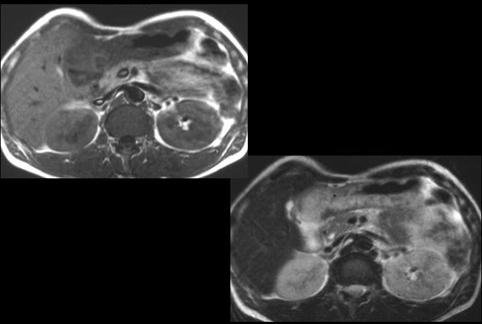

A case of gastric inflammatory disease which was suspected to be phlegmonous.

Saga Pref., Saga University Hospital (Dr.Fukuda、Dr.Mizuguchi、(Takagi Hospital Dr.Nishida))

male

60-64

Inflammatory or ulcerative disease / lesions/Others

Stomach/More than one of above

MRI